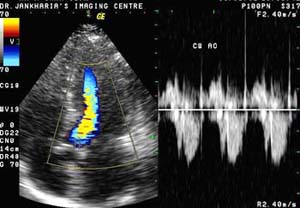

Color Doppler

What

is Color Doppler?

Color Doppler is a special ultrasound technique, which allows us to evaluate

blood vessels.

What is the principle?

Using the Doppler principle of changing pitch with velocity, ultrasound waves

that reflect from the red blood corpuscles in arteries and veins are evaluated

for velocity and amplitude and color maps of the vessels can be generated.

Is special equipment required?

An ultrasound machine equipped with color Doppler facilities is required. These

are now readily available at many centers.

What is its utility?

Color Doppler is very useful in evaluating the carotid arteries in the neck, the

heart (echocardiography), the arteries and veins in the abdomen and the arteries

and veins in the upper and lower limbs.

Echocardiography

What is echocardiography?

It is a method of studying the heart and the adjacent great vessels

using ultrasound.

What is it used for?

Echocardiography is used to study the structure and function of the

chambers of the heart, the integrity of the valves and the coverings of

the heart.

Does color Doppler help?

It allows better visualization of the vessels and the chambers of the

heart